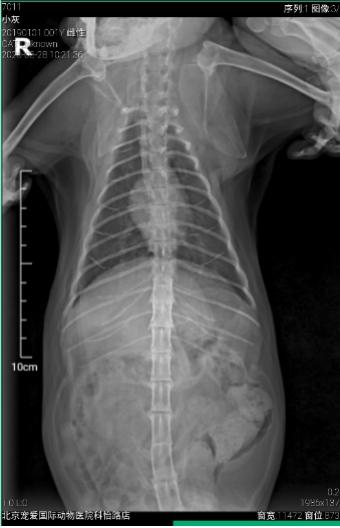

超声和DR检查

未见腹腔、胸腔内转移